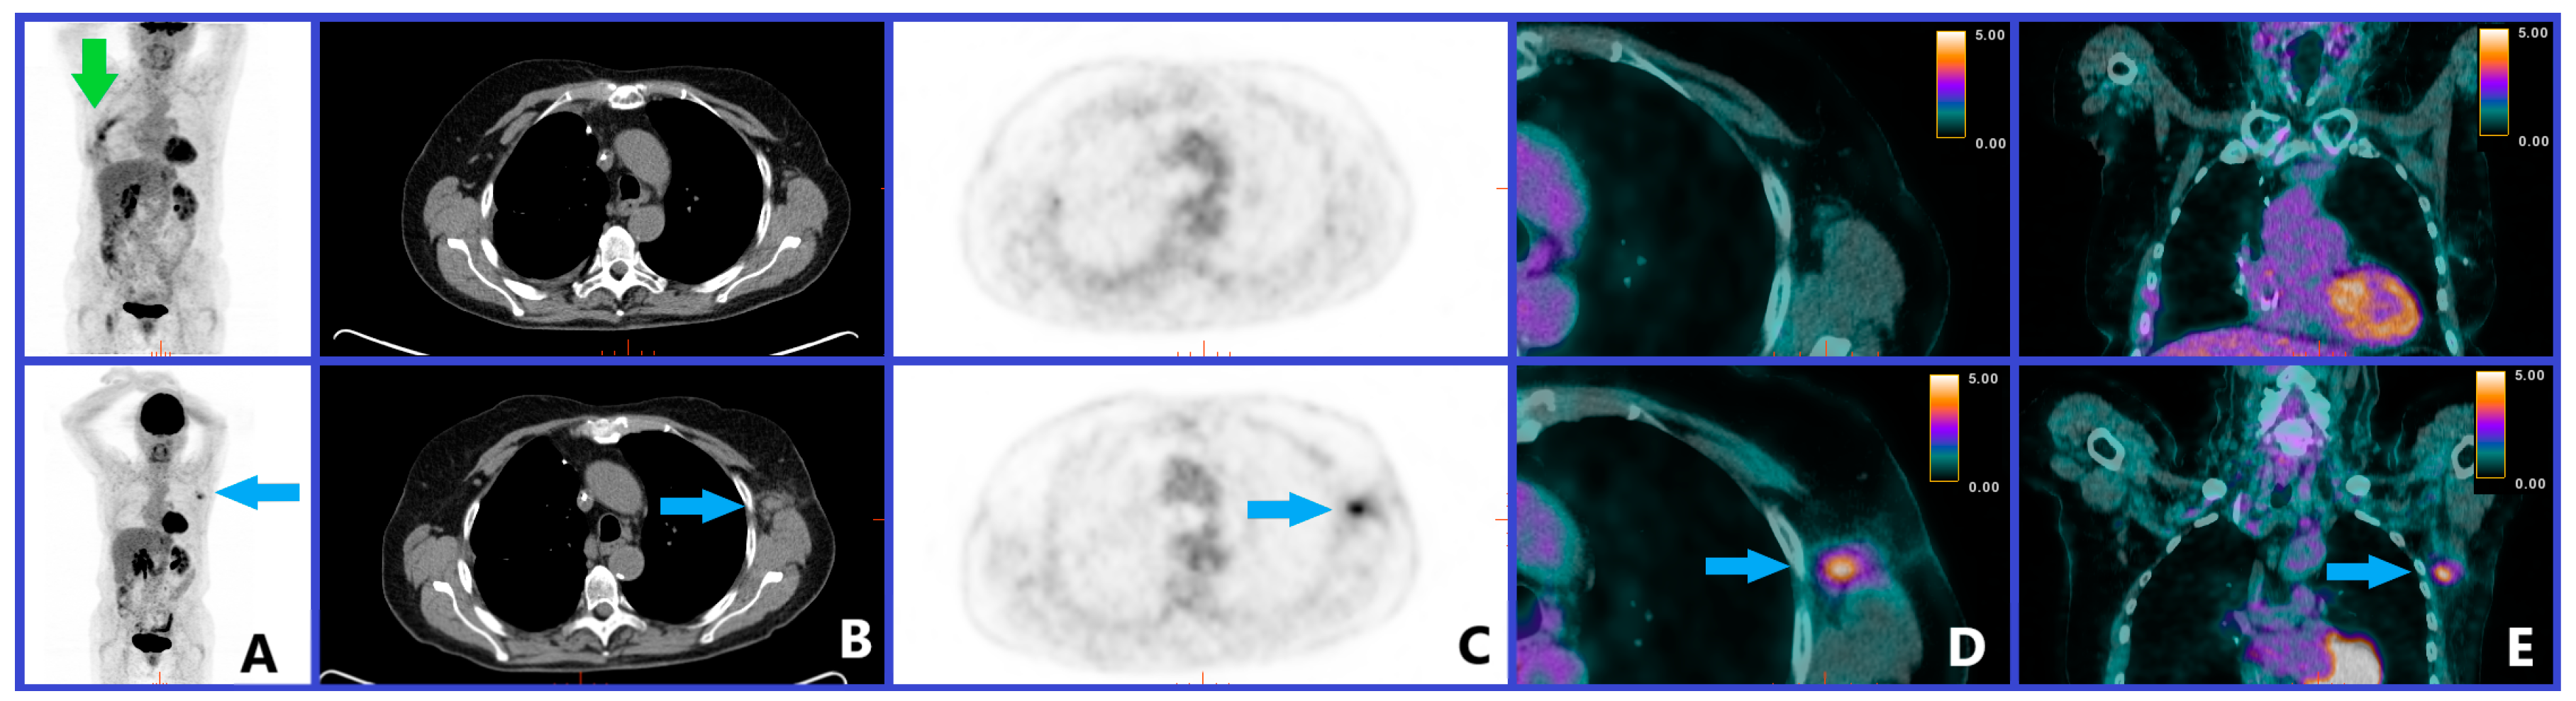

5.5. Abscopal Effect

- Britschgi, C.; Riesterer, O.; Burger, I.A.; Guckenberger, M.; Curioni-Fontecedro, A. Report of an abscopal effect induced by stereotactic body radiotherapy and nivolumab in a patient with metastatic non-small cell lung cancer. Radiat. Oncol. 2018, 13, 102. [Google Scholar] [CrossRef]